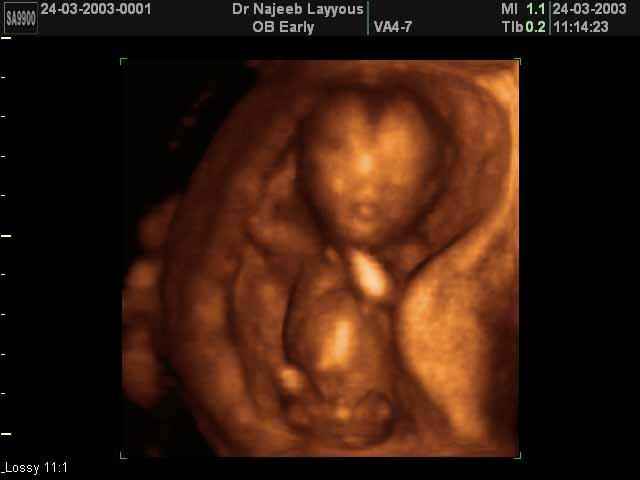

3D First Trimester Ultrasound Scan Photos